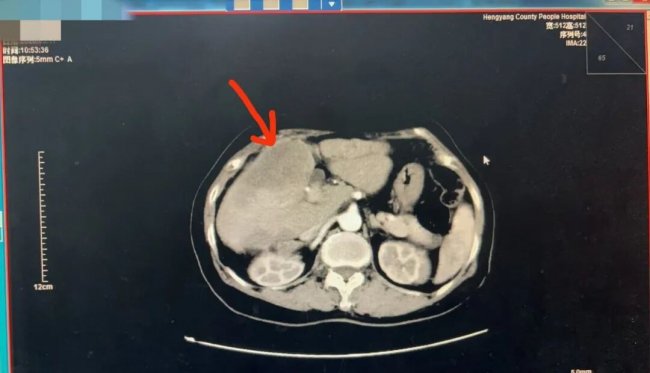

3月17日,衡阳县人民医院肿瘤内科在CT引导下,为一名61岁女性患者成功实施肝占位穿刺活检术,顺利获取病理标本,最终明确诊断为肝胆管细胞癌。

该患者因腹胀不适3月余,曾先后于南华附一、中山大学附属第一医院就诊,PET-CT提示肝多发结节并腹膜转移,考虑肝胆管细胞癌可能。3月16日,患者来到人民医院肿瘤内科就诊,予以完善胸腹部增强CT后,肿瘤内科吴娟主任、聂凡医生评估了患者的一般情况,判断其具备肝穿刺活检指征。在与患者家属充分沟通后,决定在医院完成此项检查。

3月17日,肿瘤内科与放射科副主任(主持全面工作)何云强沟通协调好后,在CT引导下精准实施肝穿刺活检,全程仅用时30分钟,术后患者安返病房,未出现出血等并发症。活检标本送检后,病理科刘杰主任于3月19日出具病理报告,明确诊断为肝胆管细胞癌。目前,患者已在人民医院肿瘤内科接受免疫联合化疗等后续治疗。